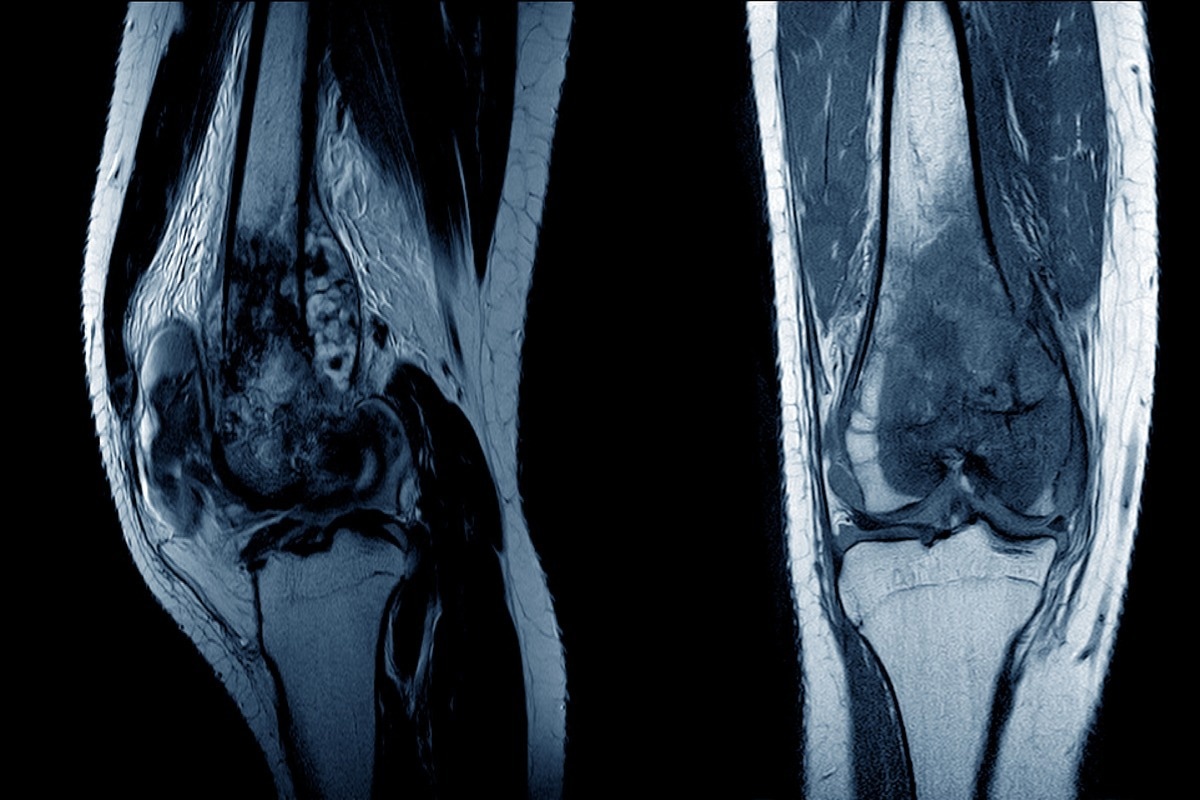

Image Credit: April stock/Shutterstock.com